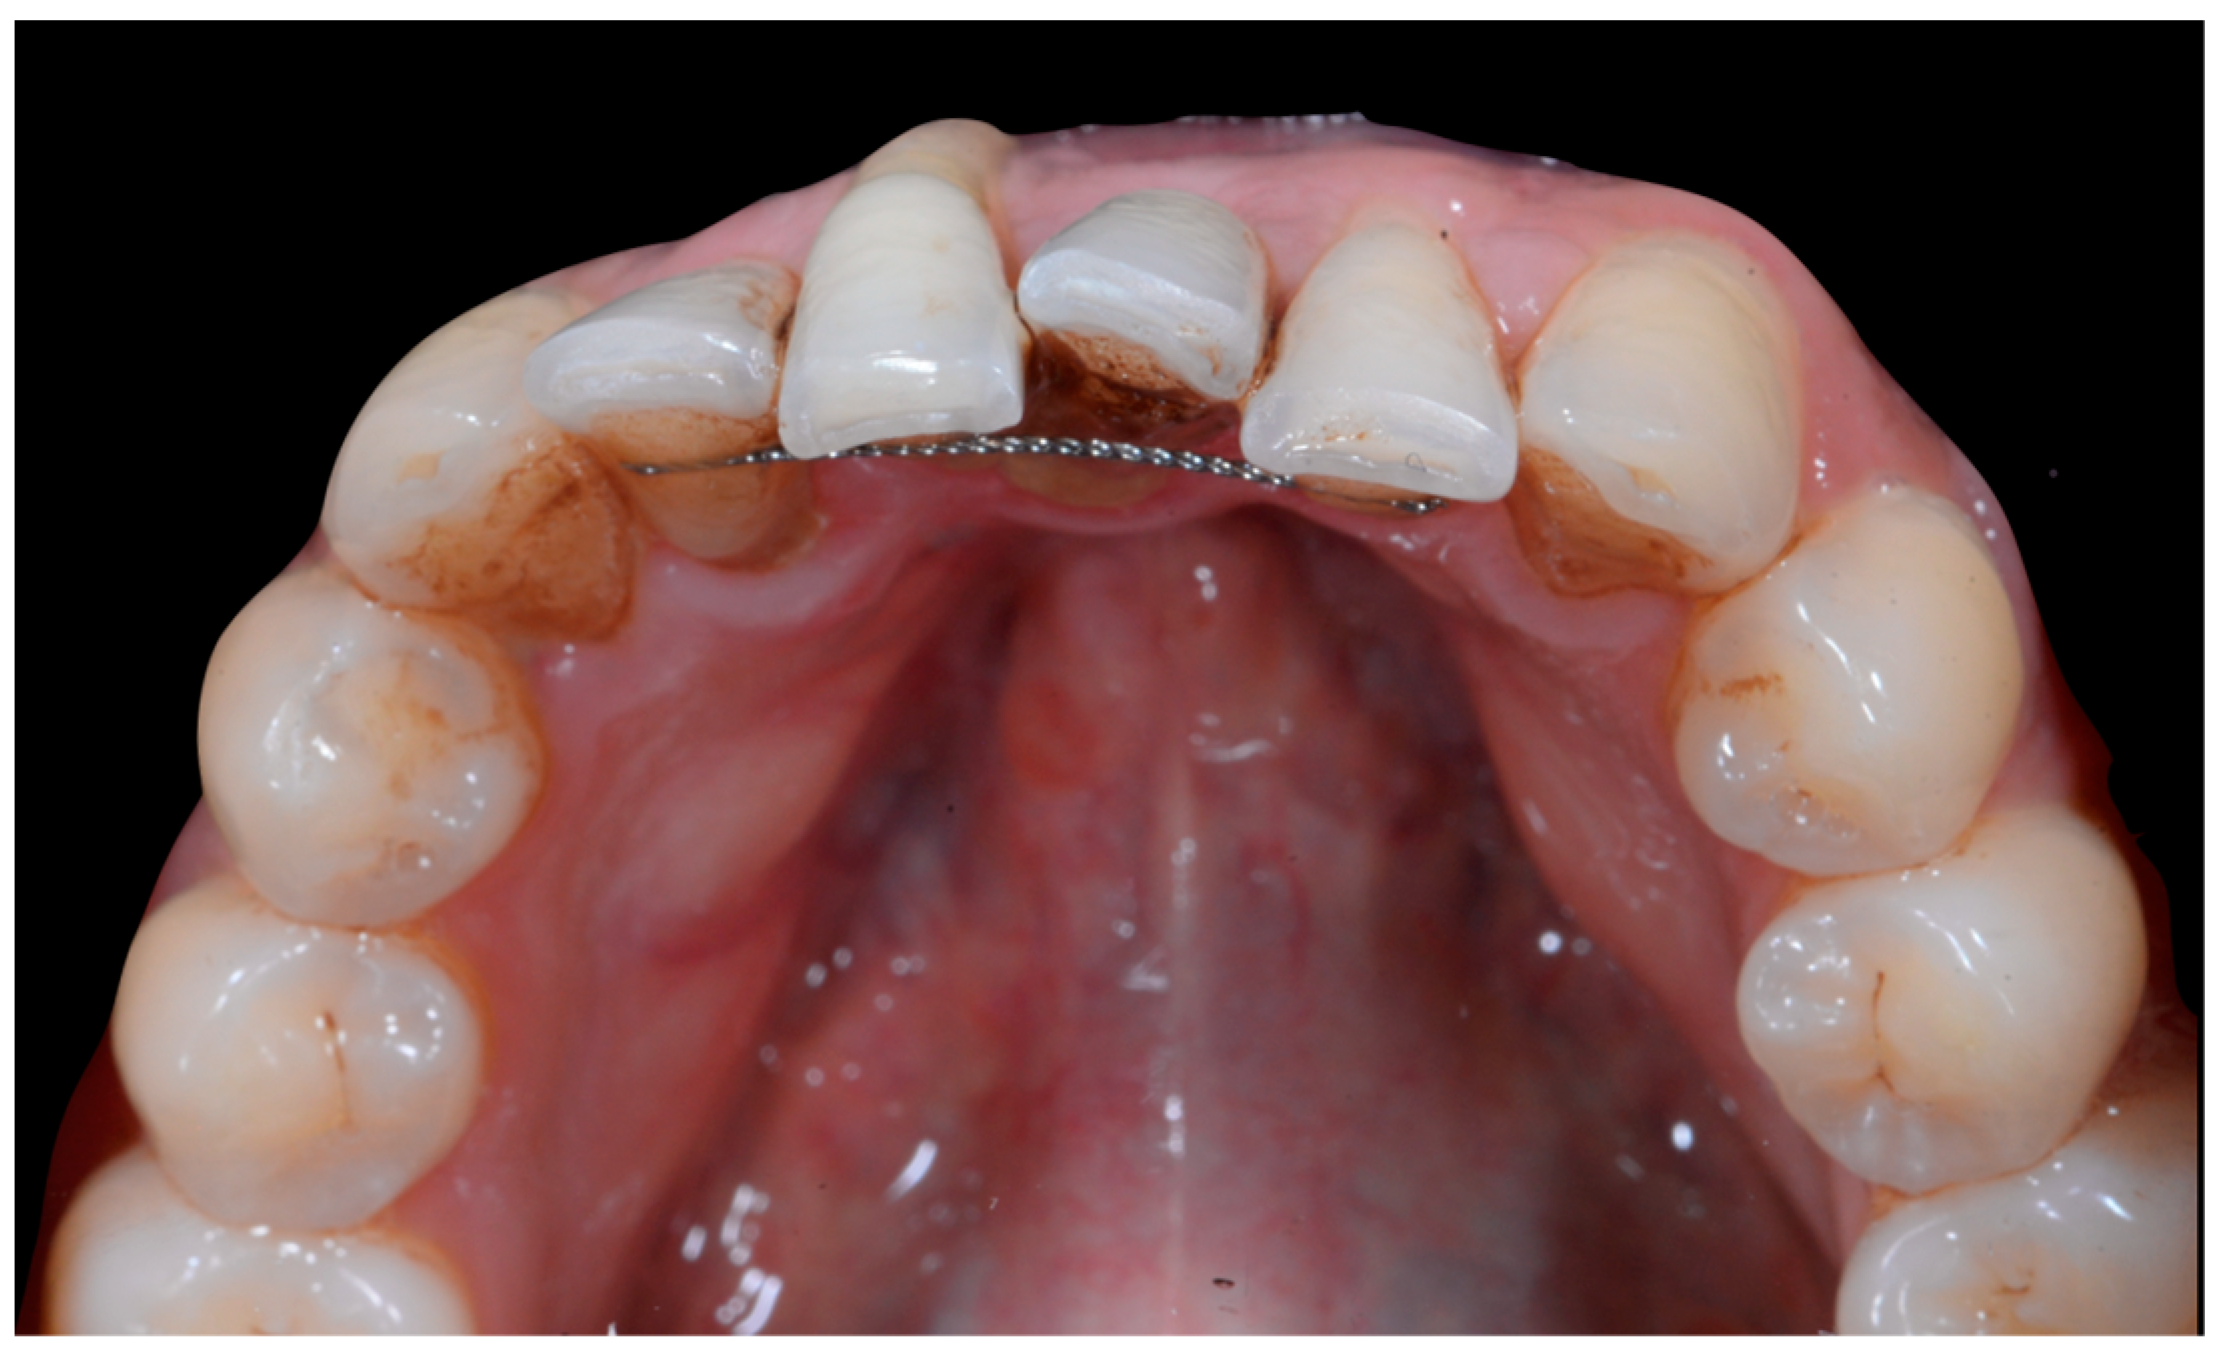

The occlusal views provide additional relevant information (Figure 9 and Figure 10). A maxillary retainer was present on 11 and 21 only and a difference in visibility of the vestibular surfaces (differential torque) on these same teeth was noted.

Figure 9.

Intermediate wire syndrome. Occlusal view.

Figure 10.

In the mandible, the retainer was broken distal to 42 and, despite being intact on 33, this tooth had increased visibility of its vestibular surface compared to its contralateral tooth (differential torque). Finally, teeth 31 and 41 also showed a difference in the visibility of their vestibular surfaces (differential torque). Ultimately, the patient was diagnosed with an X-effect wire syndrome on 21, an X-effect wire syndrome on 41, and a Twist-effect wire syndrome on 33.